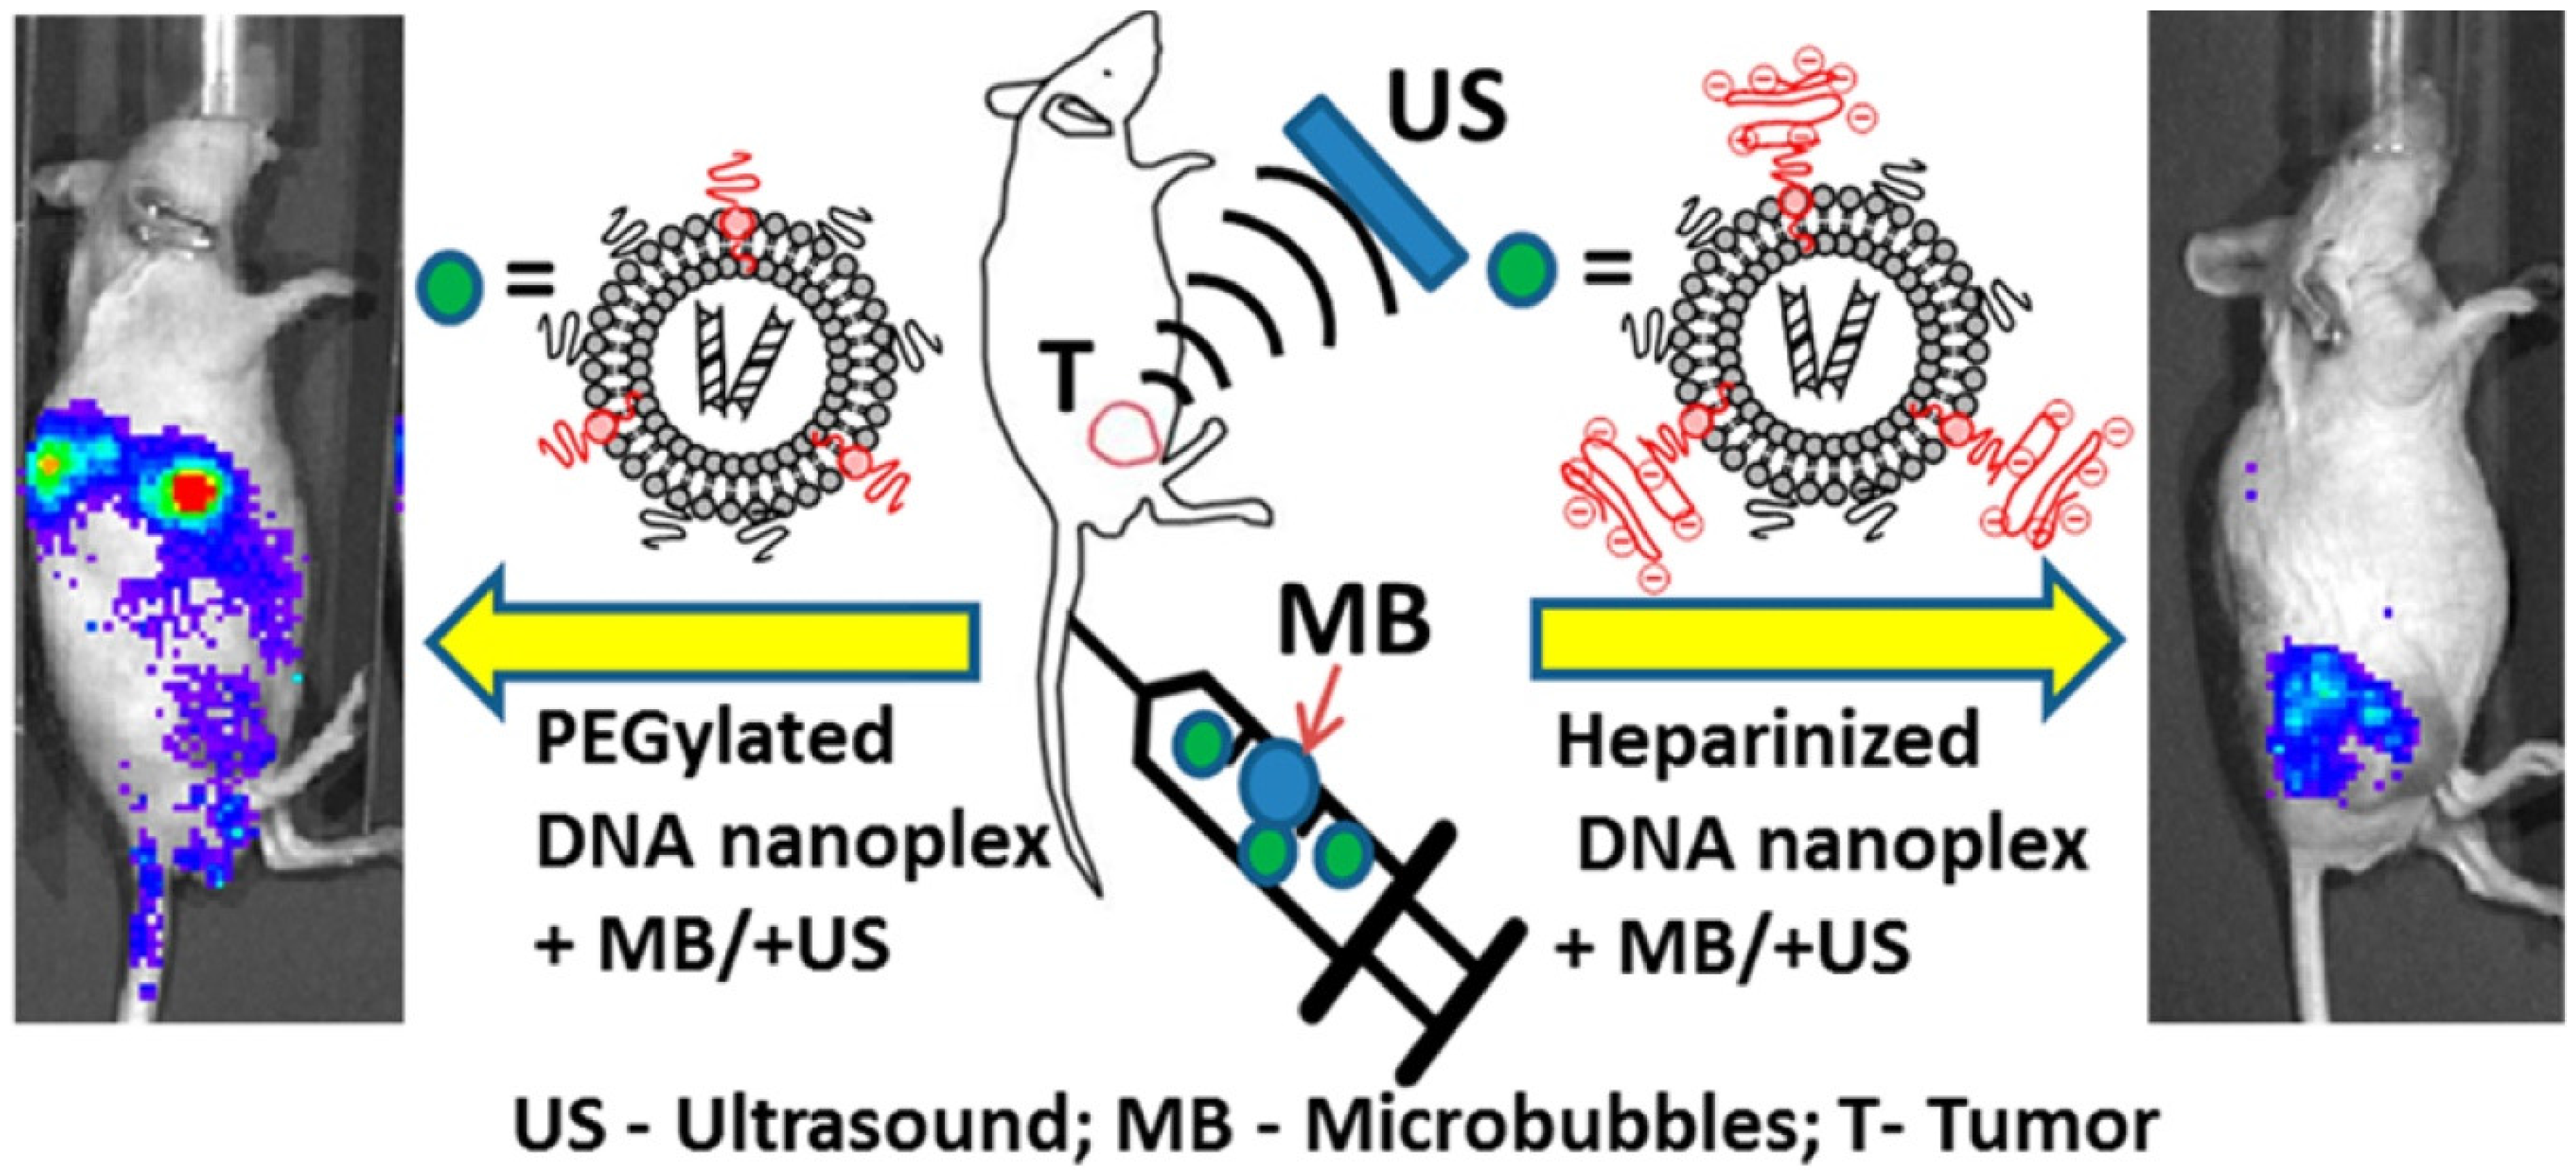

- Chertok, B.; Langer, R.; Anderson, D.G. Spatial Control of Gene Expression by Nanocarriers Using Heparin Masking and Ultrasound-Targeted Microbubble Destruction. ACS Nano 2016, 10, 7267–7278. [Google Scholar] [CrossRef] [PubMed]